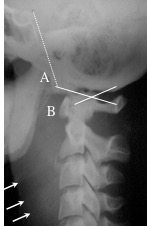

la radio standard montre un espacement entre condyles et atlas, une inversion du rapport de Powers, gun gonflement des parties molles rétro-pharyngées.

depuis l’utilisation large de l’IRM, on a noté qu’en fait les lésions traumatiques occipito-C1 non déplacées ne sont pas si exceptionnelles. il faut y penser devant une hémorragie sous-arachnoïdienne du bas de la fosse postérieure. Le traitement de ces cas est orthopédique.